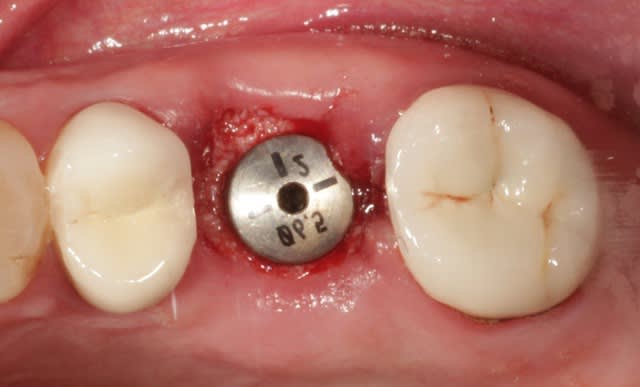

16 extraite, soulevé de la membrane sinusienne au piezo et pose d'un implant dans la foulée, comblement de l'alvéole au Bio-Oss.

non rien du tout, la vis fait 2 mm de diamètre de plus que l'implant.

C'est un 4,5mm là, j'aurais pu effectivement poser un 5mm,

1) mais ça n'aurait pas changé grand chose là

2) ça m'aurait obligé à passer un fôret dans ce cas là

3) j'avais toujours la possibilité de mettre un 5 au cas ou je n'arrive pas à stabiliser l'implant,

parce que là j'ai 3 ou 4 mm d'os maxi.